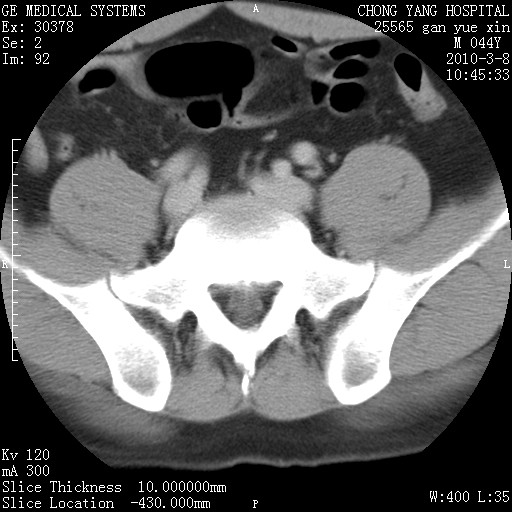

标题: CT24940:主动脉增强,典型病例。 [打印本页]

标题: CT24940:主动脉增强,典型病例。

夹层动脉瘤。

动脉夹层

夹层动脉瘤,典型

主动脉夹层。

动脉夹层的分型:

⒈debakey分型:根据主动脉夹层累及部位,分为三型:ⅰ型:原发破口位于升主动脉或主动脉弓部,夹层累及升主动脉、主动脉弓部、胸主动脉、腹主动脉大部或全部,少数可累及髂动脉。ⅱ型:原发破口位于升主动脉,夹层累及升主动脉,少数可累及部分主动脉弓。ⅲ型:原发破口位于左锁骨下动脉开口远端,根据夹层累及范围又分为ⅲa,ⅲb。ⅲa型:夹层累及胸主动脉。ⅲb型:夹层累及升主动脉、腹主动脉大部或全部。少数可累及髂动脉。

⒉stanford分型:a型:夹层累及升主动脉,无论远端范围如何。b型:夹层累及左锁骨下动脉开口以远的降主动脉。

夹层动脉瘤,少量胸水

夹层动脉瘤;左侧少量胸腔积液。

典型主动脉夹层。